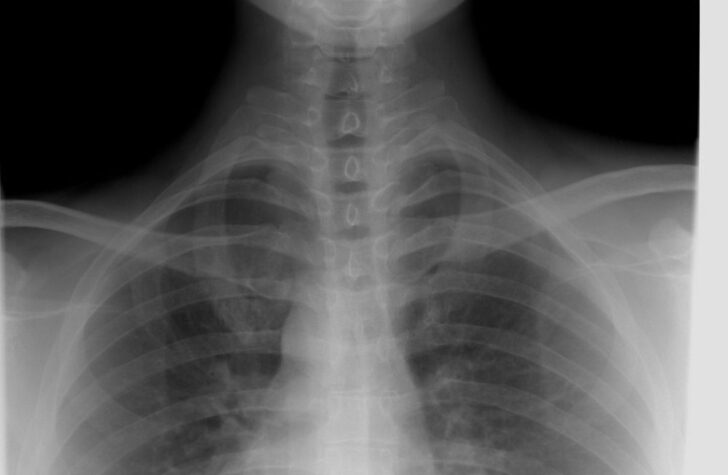

En røntgenundersøgelse er en billeddiagnostisk undersøgelse, hvor røntgenstråler sendes gennem kroppen for at skabe billeder af knogler og organer. Strålerne opfanges af en detektor eller plade, og lægen kan derefter vurdere forandringer i kroppens væv på skærmen.

– knogler og tætte strukturer fremstår lyse

– bløddele, som muskler og organer, fremstår mørkere

– luftfyldte områder, som lunger, er mørkest på billedet

– undersøgelse af brystkassen, blandt andet lunger og hjerte